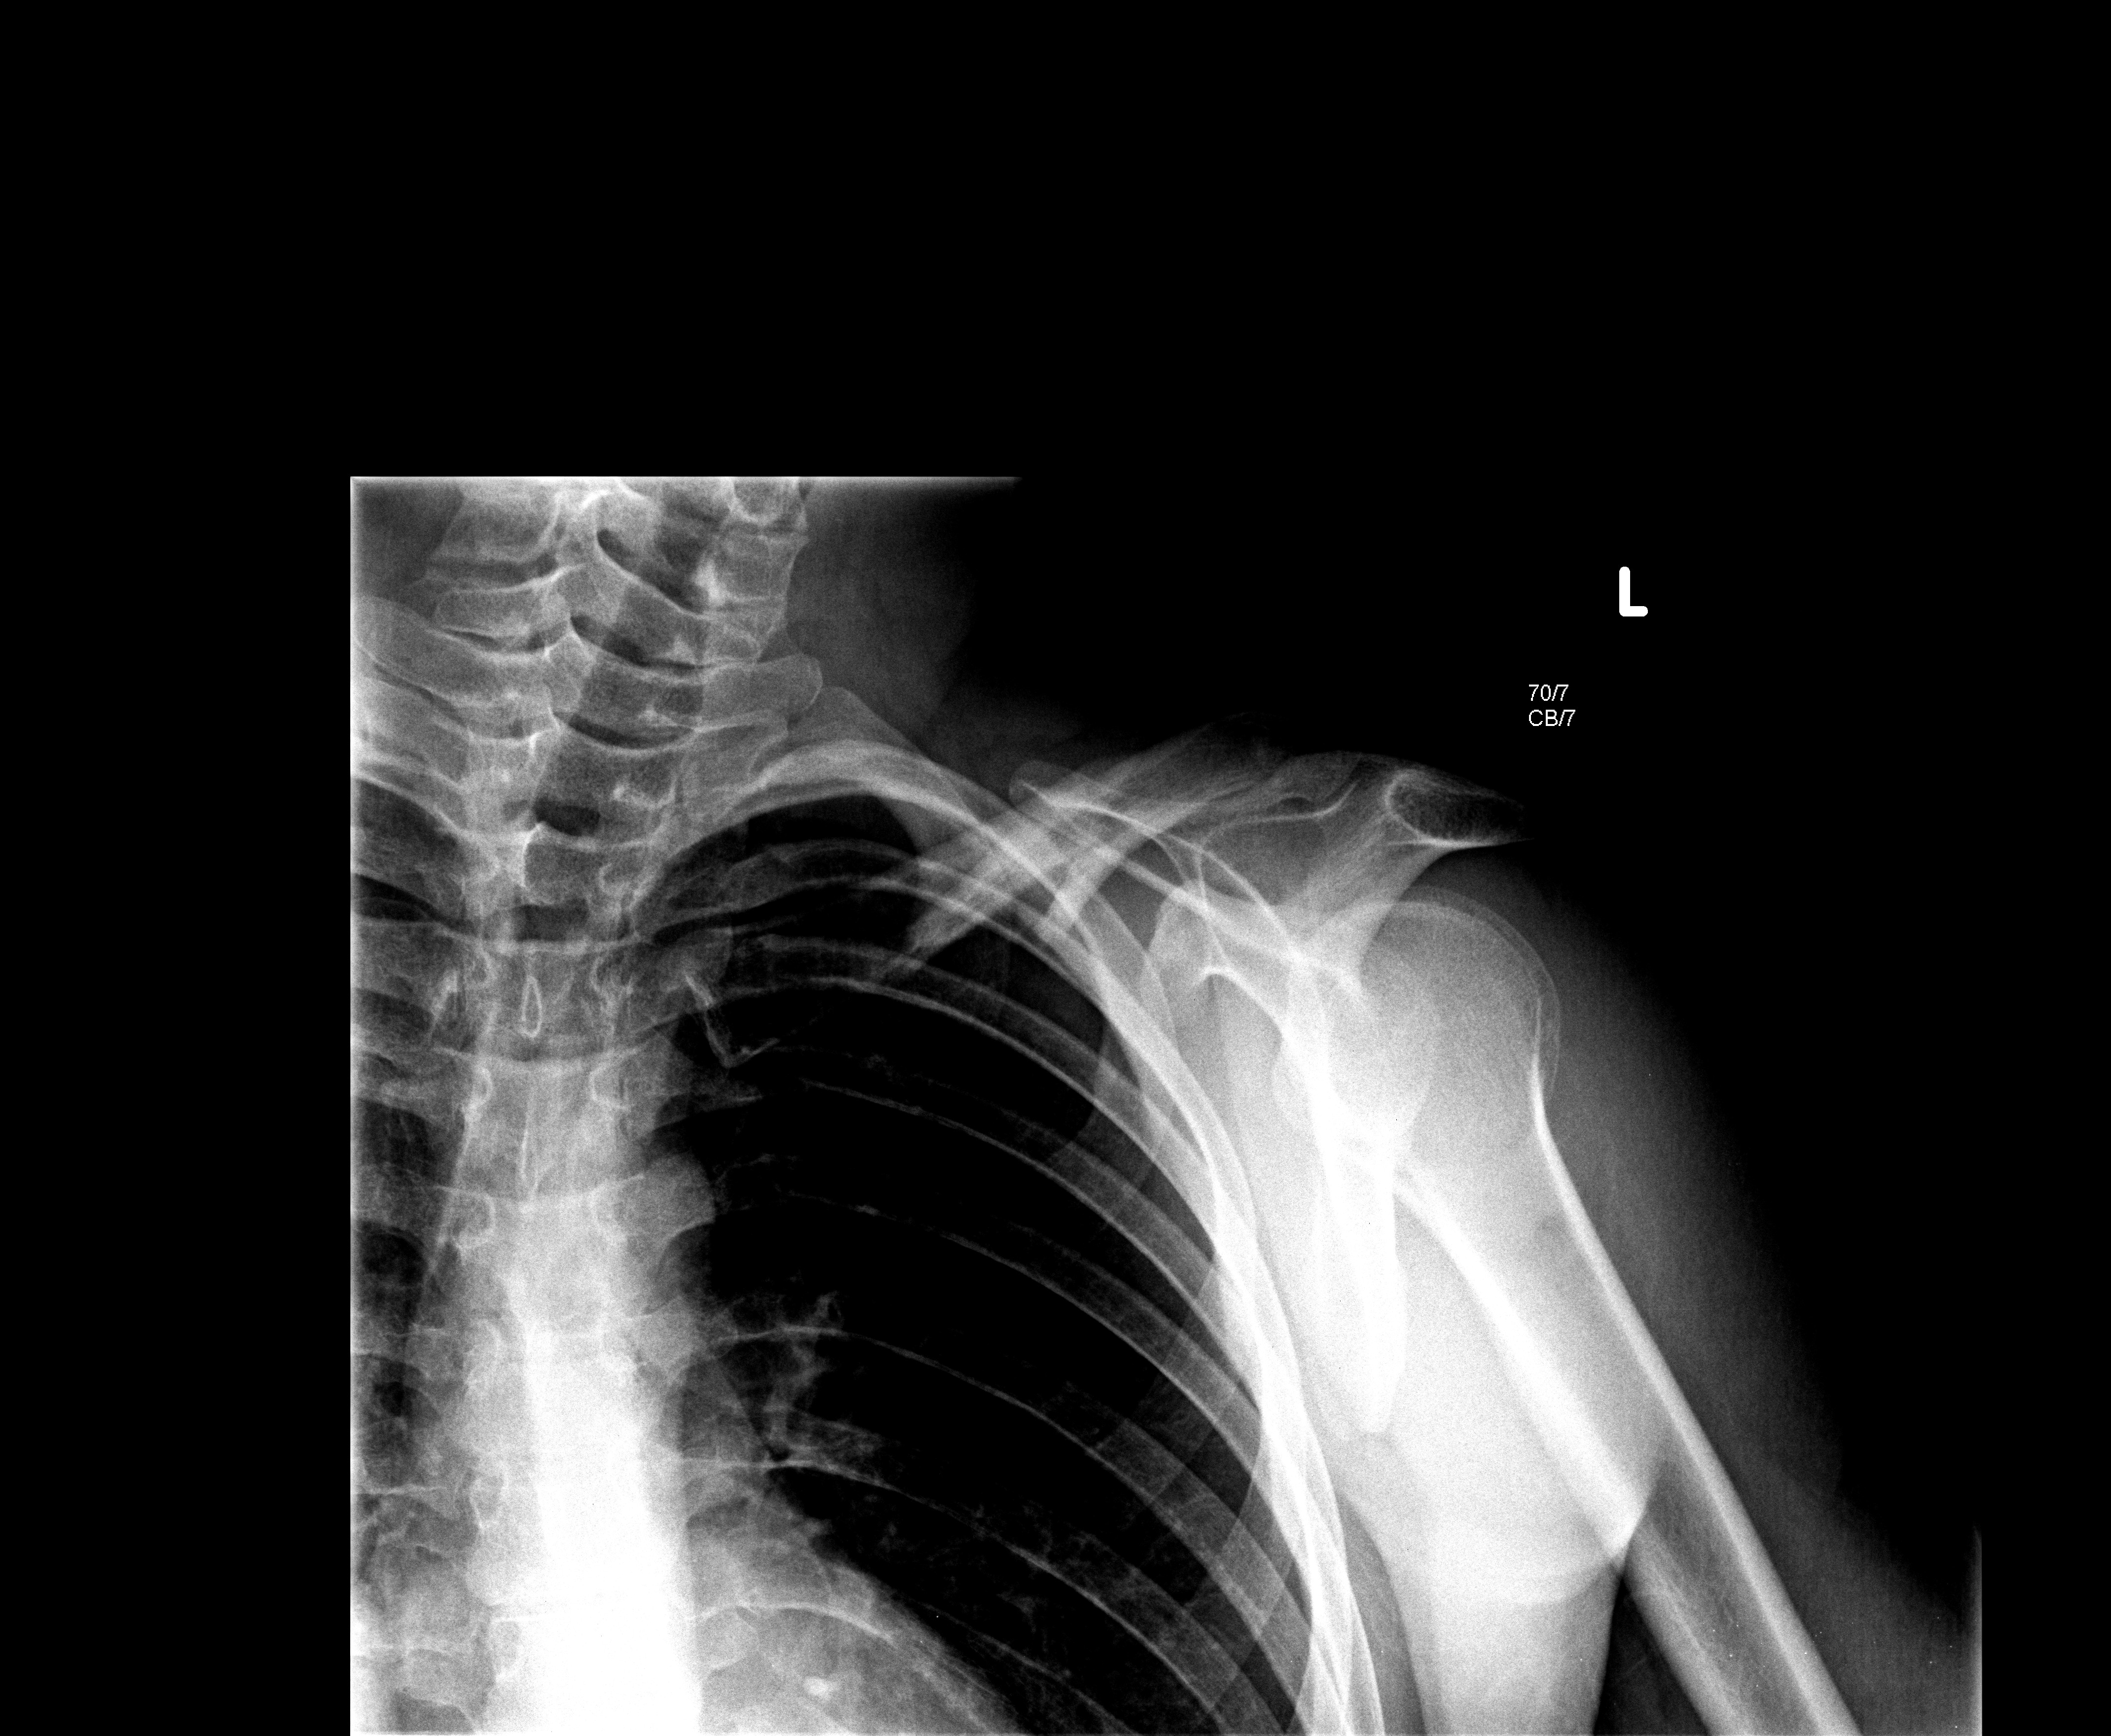

a ja wczoraj miałem szlifa :mad: obojczyk złamany i suka troche pocharatana ... az iskry szły :D